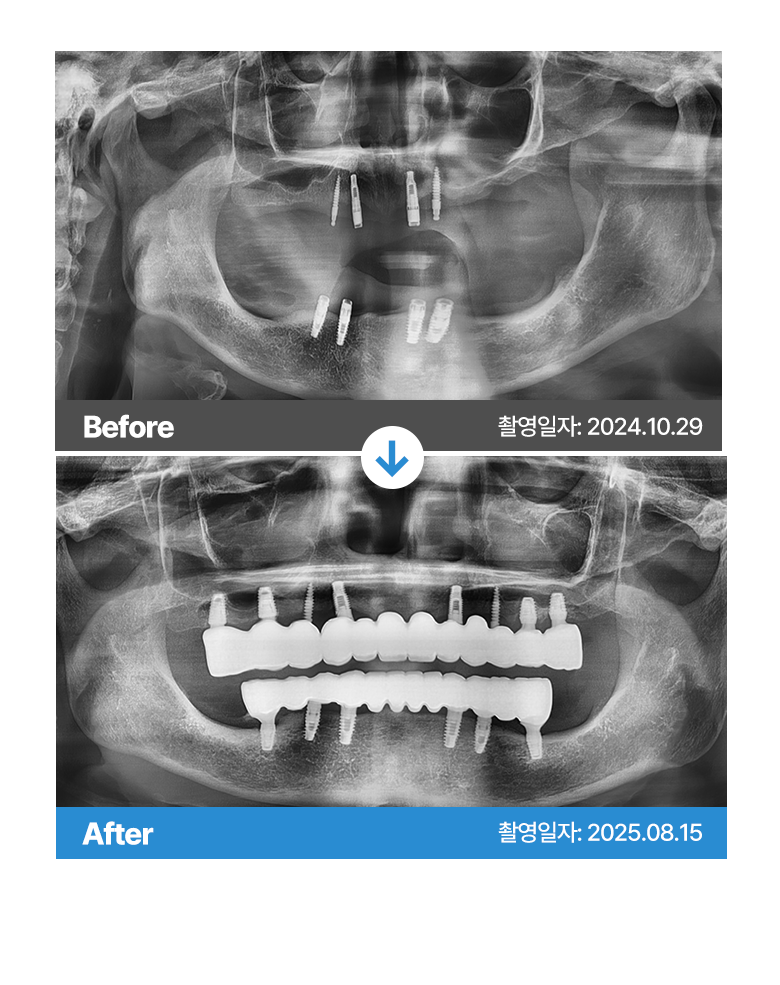

Before 사진 촬영일자: 2024.10.29 /  After 사진 촬영일자: 2025.08.15

부작용 고지: 감각이상, 신경손상, 임플란트주위염 등

* 본원에서 치료 받으신 환자분의 사례로 2차적인 가공이 없으며, 환자분의 동의를 얻어 활용함을 안내드립니다.

개인에 따라 결과차이, 부작용 등이 발생할 수 있으므로 의료진과의 상담을 통해 신중히 결정하시기 바랍니다.